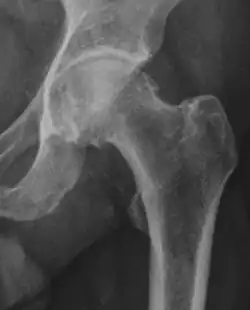

X-ray

Projectional radiography ("X-ray") is often considered first line for FAI.[10] Anterior-posterior pelvis and a lateral image of the hip in question should be attained.[10] A 45-degree Dunn view is also recommended.[10][19]

| Femoral head-neck offset | ![]() |

Offset of the femoral head with regard to most prominent aspect of the femora neck | >10 mm |

| Offset percentage | Femoral head-neck offset related to femoral head diameter | >0.18

| |